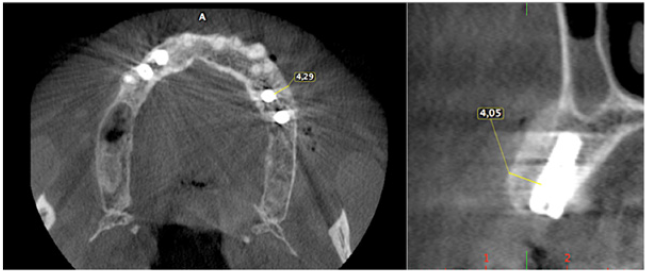

The surgery ended with 5/0 Polypropylene horizontal mattress sutures (Aragò, Barcelona, Spain). Amoxicillin 500mg every 8 hours for 7 days, Ibuprofen 600mgx3 for 3 days, Chlorhexidine 0.20% rinses morning and evening for 7 days were prescribed as postoperative medication. Postsurgical CBCT demonstrates a buccal augmentation of 4.05mm. The sutures were removed after 2 weeks of uneventful post-operative course (Figure 1-7). Six months after surgery, the clinical aspect showed an excellent volume of convex shape and hard consistency. The CBCT highlighted a horizontal gain of 4.05mm with initial mineralization. The day of re-entry the area displayed a new anatomy. The mesial implant was covered with hard tissue reproducing the shape of the cover-screw. A biopsy was taken and stored in 10% buffered neutral formalin and sent for histological examination. Healing abutments were connected and soft tissue sutured in place. After 3 months a prosthetic restoration was performed by means of a gold-ceramic screwed bridge. The histological result showed newly formed trabecular bone, in close contact with residual particles and osteoid matrix where newly formed blood vessels and active osteoblasts were present. There were not inflammatory or necrotic cells. Three years after surgery, the clinical and CBCT control show hard and soft tissue stability. The horizontal measurement of new vestibular bone is stable at 4.05mm. The peri-apical rx shows no marginal bone loss. Four years after surgery, a significant finding was observed on the new CBCT: the graft appeared almost totally reabsorbed in favor of new bone which has a radiological quality similar to that of the native bone and there is a new mature cortical plate [21] similar to the palatal native bone (Figure 8-15).

Figure 7: Post-operative CBCT.

Figure 9: Horizontal increment of 4.05mm. Initial mineralization of newly formed bone (arrows).

Figure 13: Maintenance of horizontal gain (4.05mm). No bone loss at implant platforms.